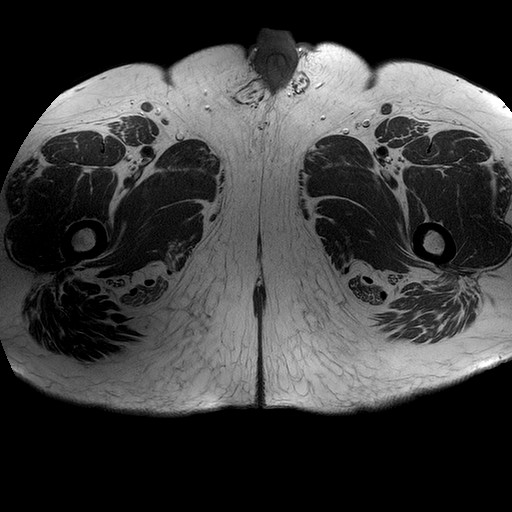

Esami: RMN BACINO

T1W_TSE

Evidenti e simmetriche alterazioni osteofitosiche in regione coxo femorale con riduzione delle rime articolari. Degenerazione completa del cercine glenoideo. Non attuali segni di versamento articolare. Non segni di edema osseo che escludono attuale algodistrofia od osteonecrosi. Lieve e simmetrica riduzione del trofismo della muscolatura glutea.